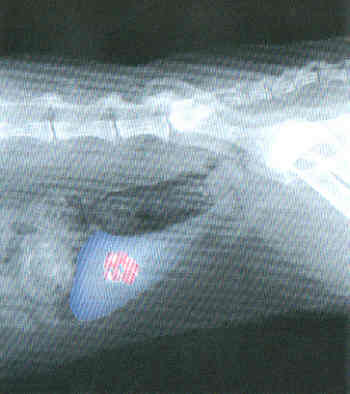

Blasensteine, Röntgenbild

Die meisten Blasensteine können durch eine Röntgenaufnahme entdeckt werden. Für die weitere Behandlung ist eine genaue Analyse der Blasensteine erforderlich.